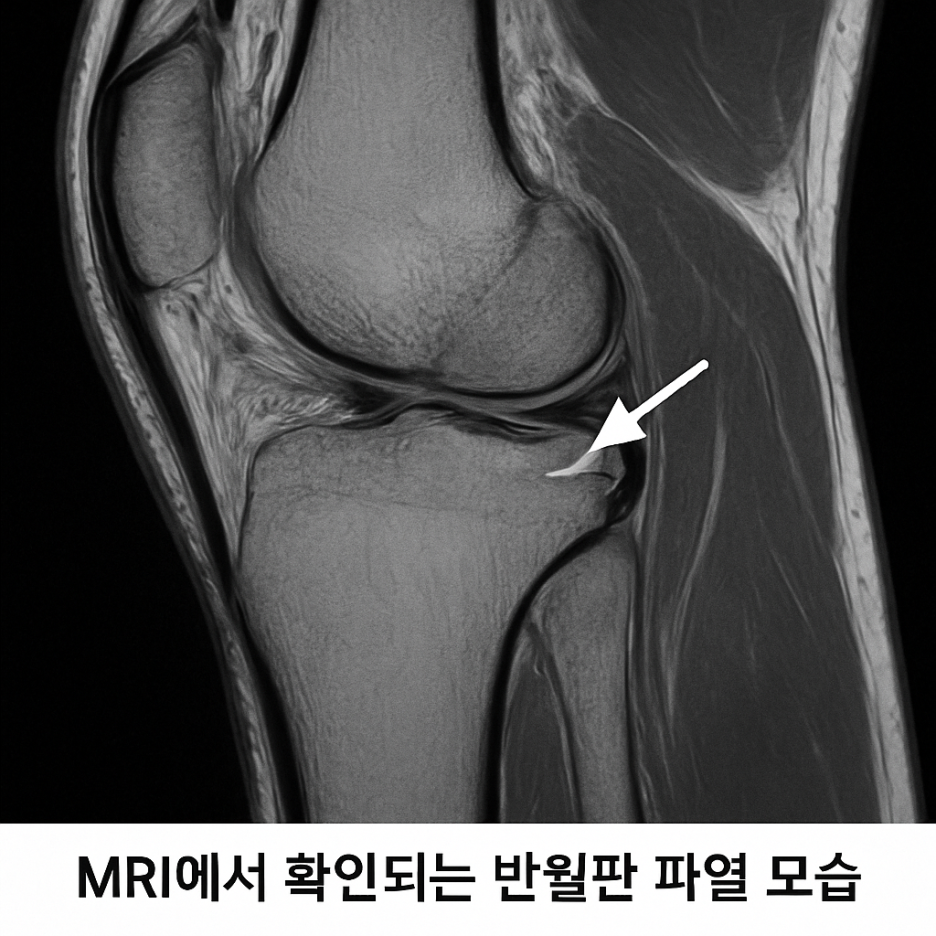

진단은 주로 병력 청취와 이학적 검사, 그리고 MRI 촬영으로 이루어집니다.

MRI는 반월판의 위치와 파열 모양을 정확히 보여주며,

손상 정도를 객관적으로 판단할 수 있는 대표적인 검사입니다.